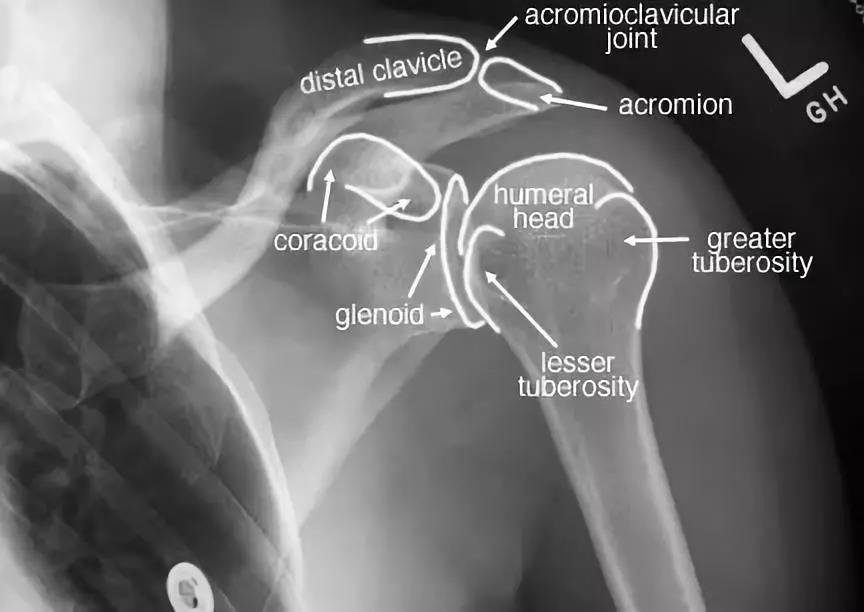

Anatomically labelled AP shoulder xray. Medical anatomy, Medical knowledge, Radiology student Shoulder X Ray Internal Vs External Rotation diagram of internal rotation of the shoulder. The affected arm is internally rotated. Two ap views should be obtained, one with the humerus in external. The red arrow points to the lesser tubercle of the humerus in profile. the infraspinatus and teres minor are assessed by having the patient resist external rotation pressure with the arms held at. Shoulder X Ray Internal Vs External Rotation.